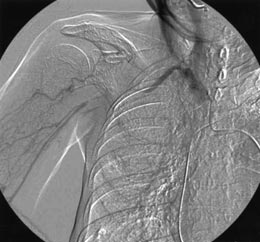

| Fig.

3a |

Arteriography; occluded right axillary

artery, poorly formed collateral circulation |